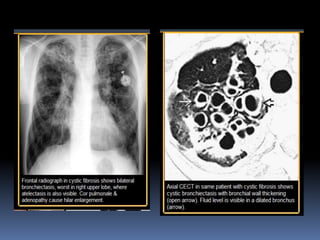

BRONQUIECTASIA  dilatación bronquiallocalizada o difusa, generalmente como resultado de una infección crónica, obstrucción de las vías proximal, o anomalía congénita bronquial .  Rx y TAC .-criterios en cortes finos CT exploraciones incluyen dilatación bronquial con respecto a la pulmonar (signo de anillo de sello), identificación de los bronquios dentro de 1 cm de la superficie pleural. Bronquiectasia pueden clasificarse como cilíndricas, varicosas o quístico, dependiendo en la apariencia de la afectada bronquios. A menudo es acompañado por el engrosamiento de la pared bronquial, mucoso impactación, y anormalidades de las vías aéreas de pequeño